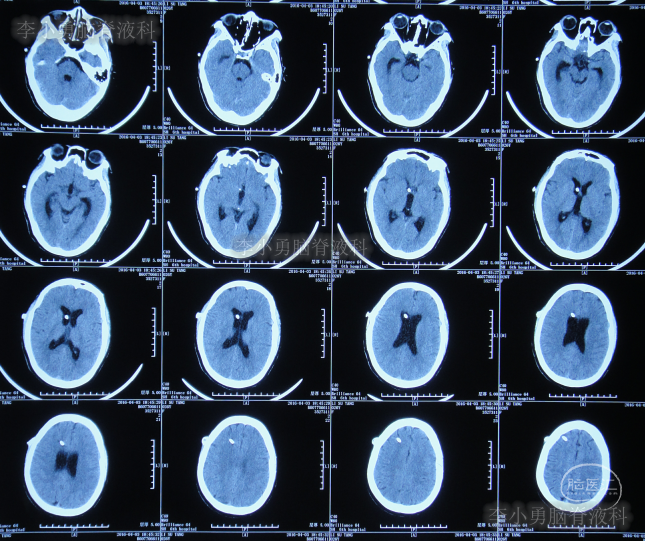

第三家医院第2次建议回家观察1周后即2016年4月3日,症状仍未缓解反而越来越重,于是,就诊于第四家位于上海市徐汇区的某三甲医院,查头颅CT后(图-2)“认为无明显异常”,怀疑癫痫。

图-2:2016年4月3日头颅CT